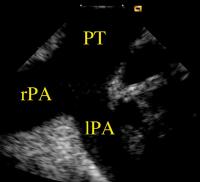

Figure 9: Left and right pulmonary arteries viewed with the AcuNav (TM)-catheter in the pulmonary trunk. lPA = left pulmonary artery; rPA = right pulmonary artery; PT = pulmonary trunk

Keywords: Arteria pulmonalisArteria pulmonalisCatheterechocardiographyEchokardiographieKatheterTruncus pulmonalisTruncus pulmonalis